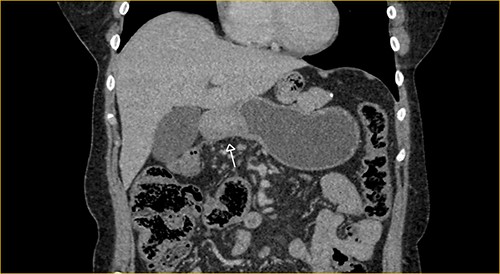

Laboratory examination showed anemia. An excluded stomach distention and parietal thickening of the pylorus and antrum were identified during abdominal computed tomography (CT) and magnetic resonance imaging (Figs 1–4). Thoracic CT was normal.

Portal phase coronal section image on CT showing excluded stomach distention with parietal thickening of the pylorus and antrum (arrow).